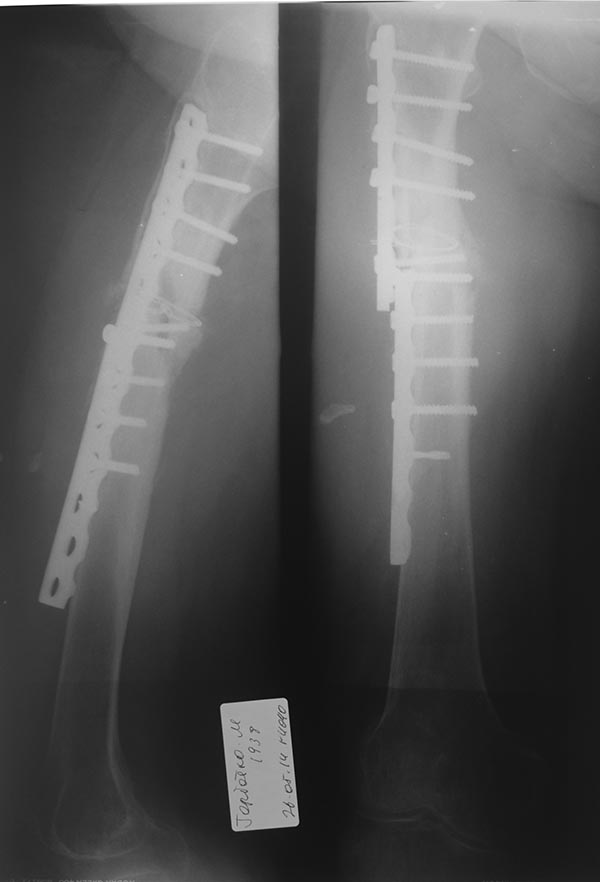

[Ortho] несращение бедренной кости+перелом импланта

Добрый вечер уважаемые коллеги. Поступила женщина 1938г.р.

С жалобами на боли,каковость в области правого бедра. Страдает сахарным

диабетом. Из анамнеза 9 месяцев назад в ЦГБ была прооперирована по

поводу оскольчатого перелома бедренной кости. 2месяца назад появилась

боль в области перелома.Повторно обратилась в ЦГБ, назначено было

консервативное лечение. В данный момент п/о рубец без воспаления (20

см), бедро отечное, пальпаторно умеренно болезненное. Передвигается с

трудом с помощью ходунка. По вечерам субфебрильная температура до37,5.

Сегодня взяли анализы: ОАК, лейкоформула,СОЭ, СРБ

Планируем:

1) удалить пластину из минидоступа

2) рассверливания КМК

3) БИОС с динамической фиксацией в проксимале

Уважаемые коллеги, какова ваша тактика лечения в данном случае, нужны ли

АБ бусы и АБ спейсер.